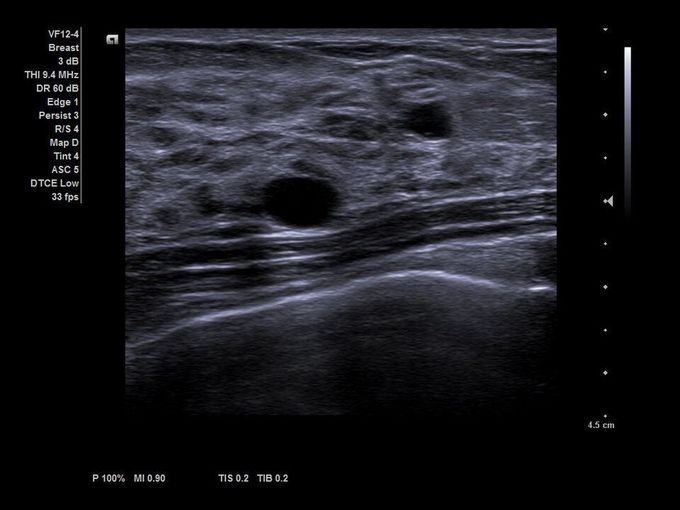

Кроме новой техники, можно заказать восстановленные медицинские системы: ультразвуковые сканеры, томографы, флюороскопы, ангиографы и хирургические установки С-дуга.